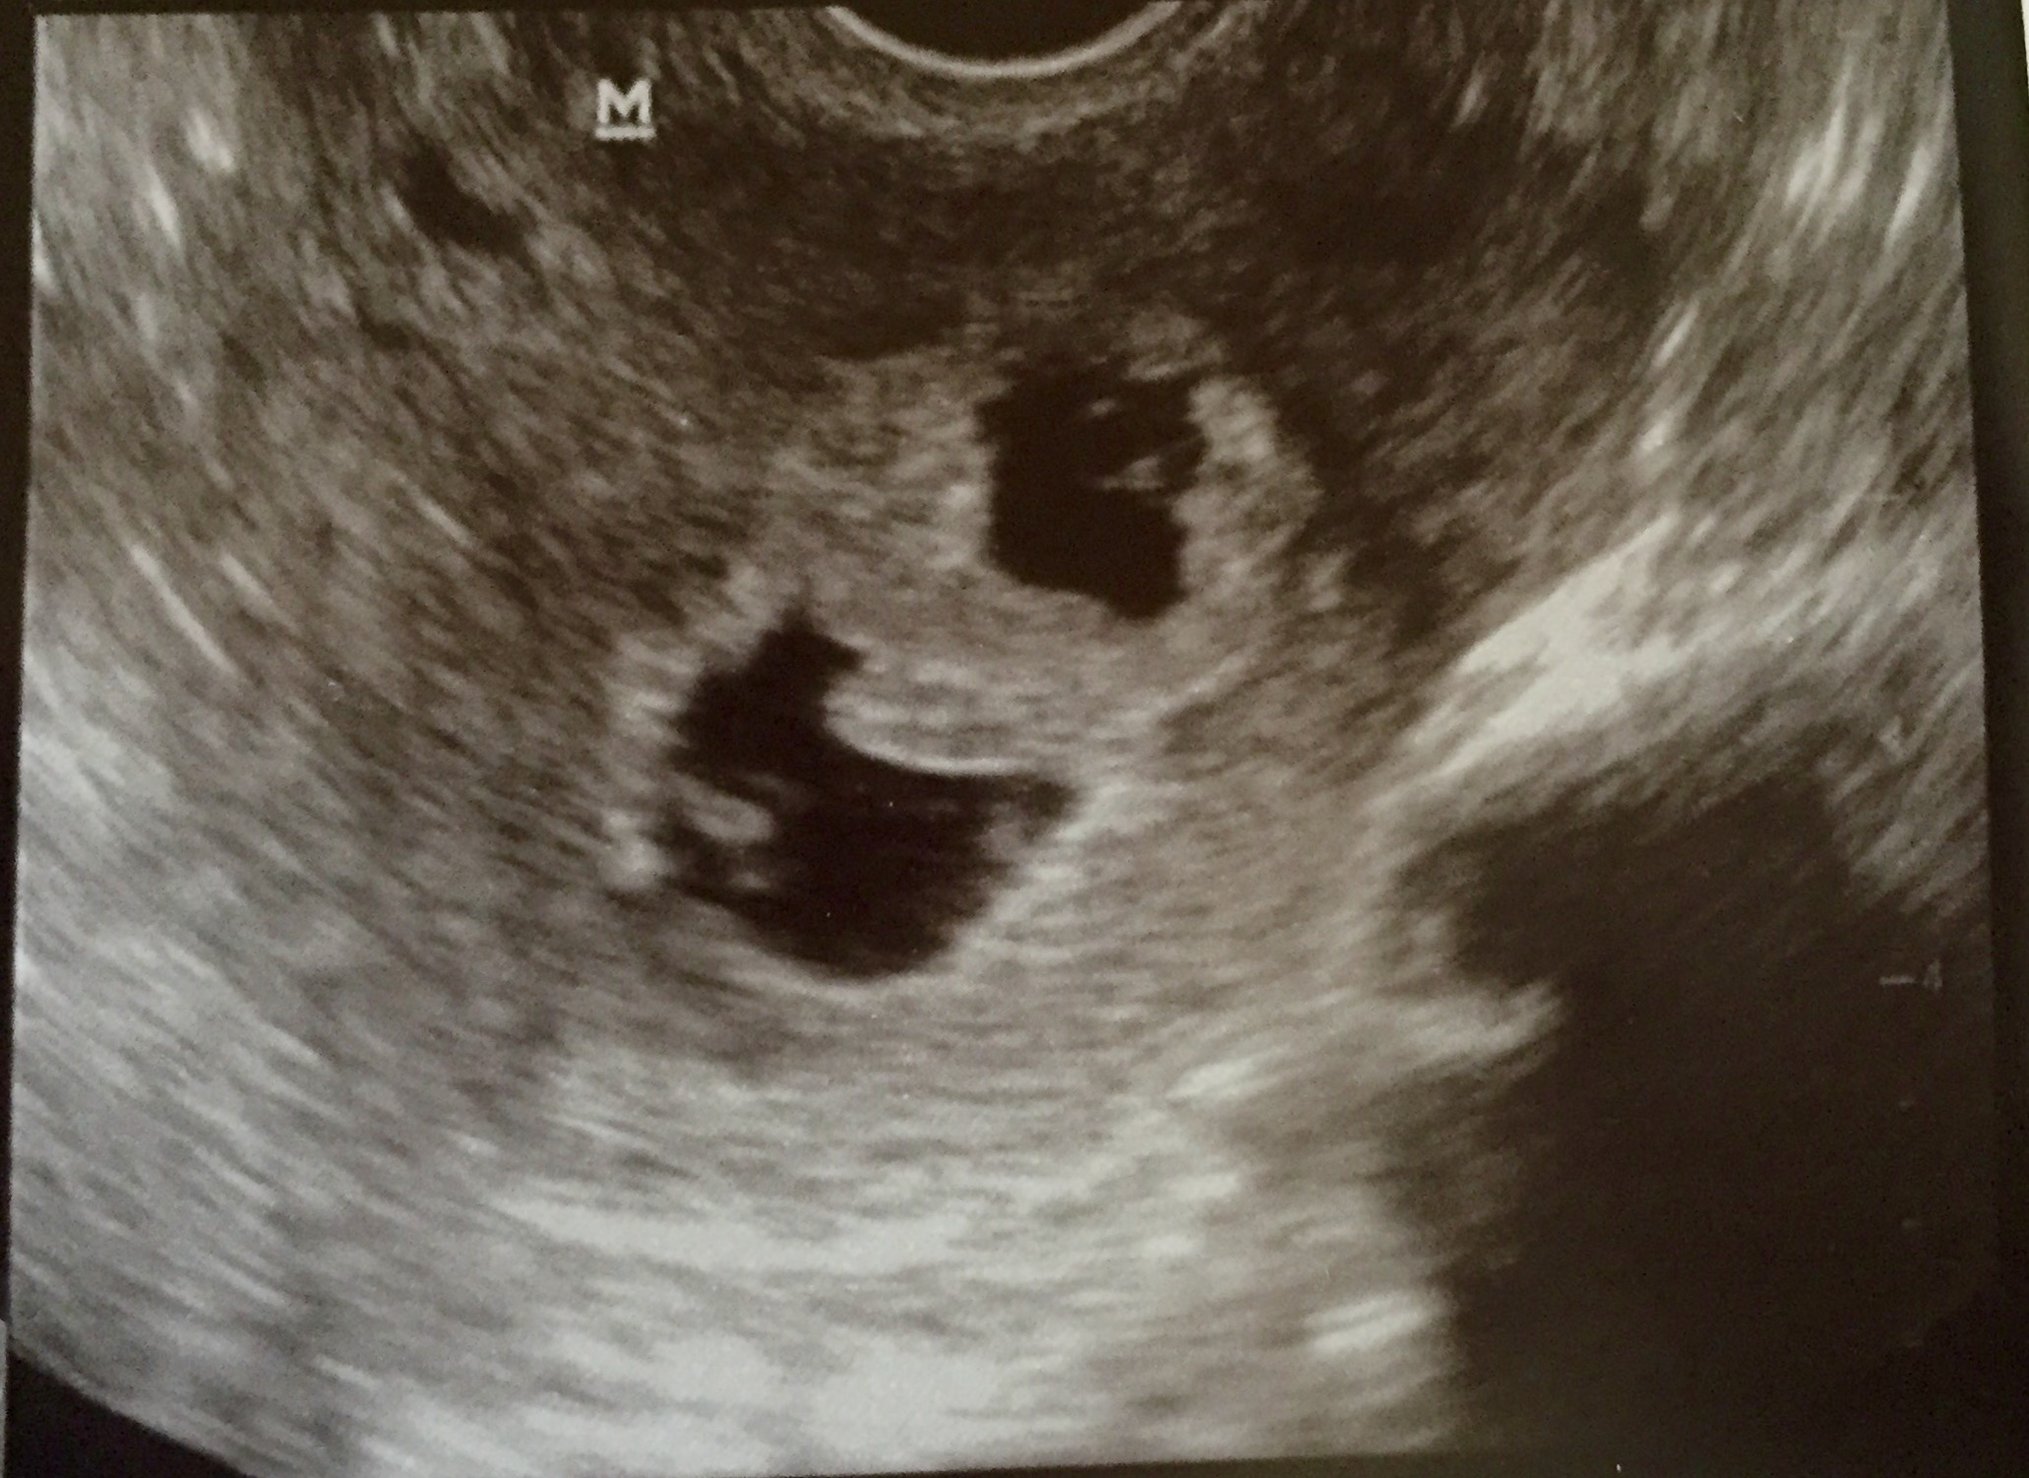

ultrasound today at 6w0d....

2 gestational sacs, 2 yolk sacs, 2 fetal poles, and 2 heartbeats!

There was a small subchorionic hemorrhage around baby A that hopefully goes away, and heartbeat for A was 98 (measuring 5w5d) and heartbeat for baby B was 90 (measuring 6w0d)...so here's hoping they keep growing bigger and stronger until we get to look in on them again next week!